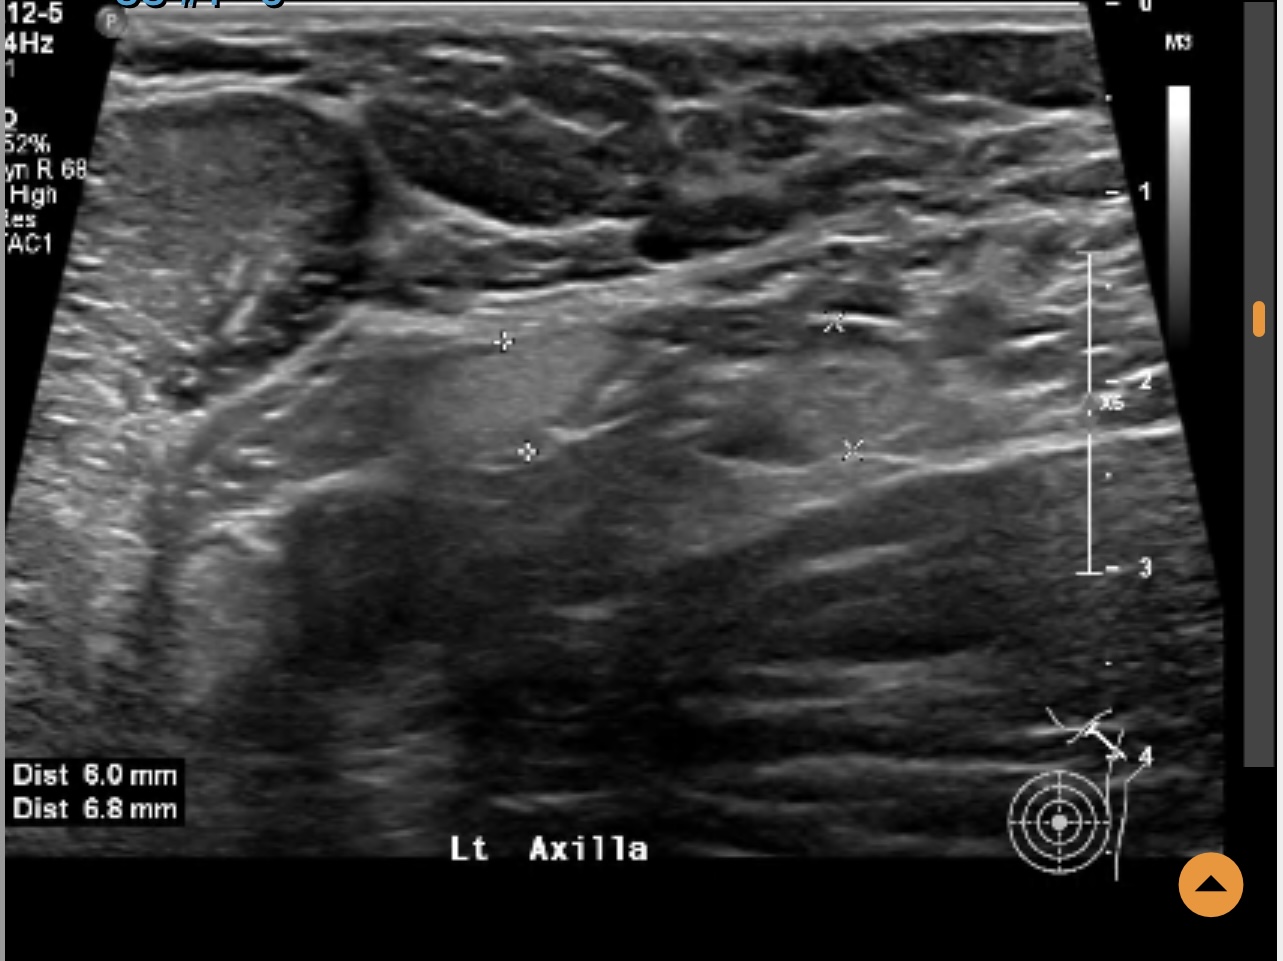

Left breast ultrasound report said no concerns. Symptoms - enlarged lymph nodes left breast, small cyst, changes in size and shape of left breast, dimples in lower left breast, pain in outer quadrant of left breast. Second opinion on ultrasound pics?